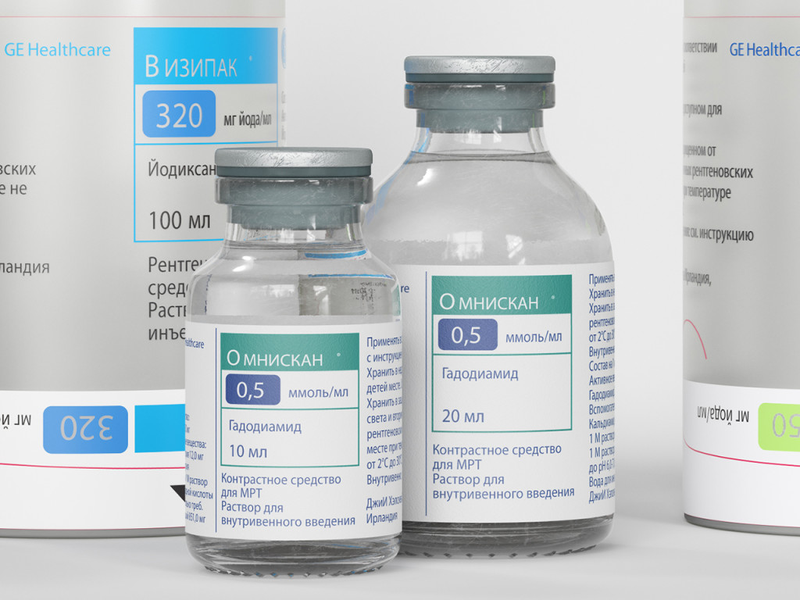

Методы динамического контрастирования печени на МРТ